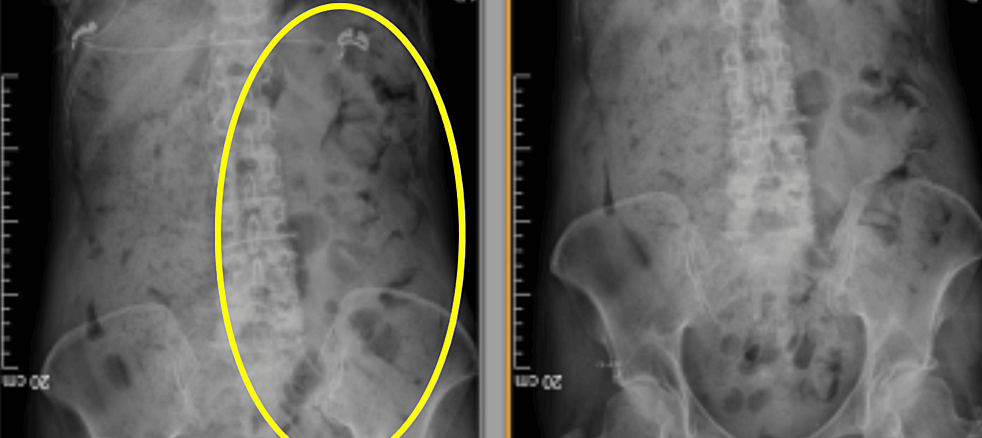

colonic transit scan

- Follow-up X-rays: You return 6 hours later on the same day for a 10-minute picture of your stomach. Then, on the next 4 days (Tuesday – Friday), you return each morning for a further 10-minute picture of your stomach. You should stay off your bowel medications and have a normal diet during this time.

- Completion & Analysis: Colonic transit is considered normal if all the markers have passed within 5 days. If markers are retained in certain areas, it suggests slow transit constipation or motility issues. A radiologist will analyse the images and prepare a report for your doctor.